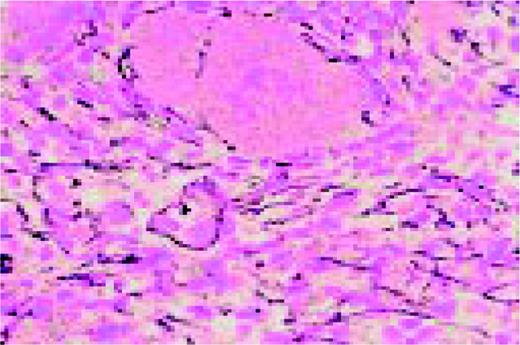

Slide E8

Agnogenic myeloid metaplasia with myelofibrosis. This low-power bone marrow biopsy clearly shows the fibrosis associated with this disease. This H&E-stained preparation shows virtual replacement of the marrow cavity with light pink-staining fibrotic tissue.FIG104